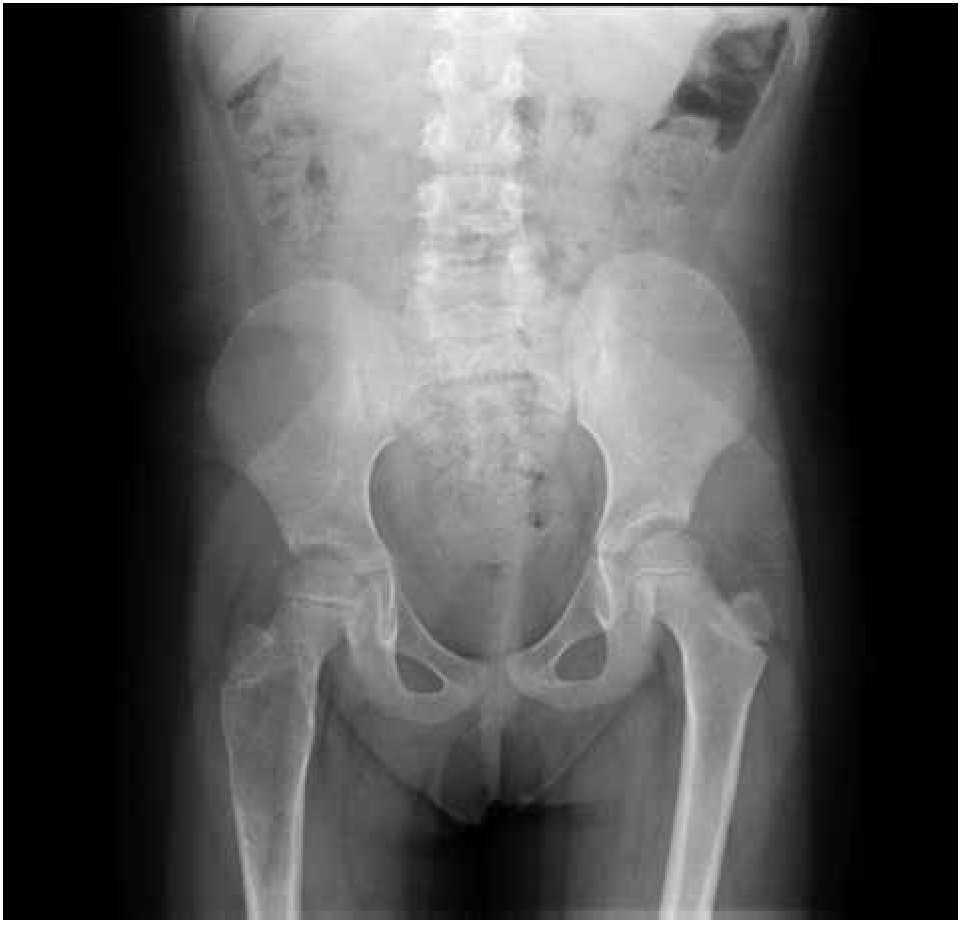

Paciente femenina, quien a los seis años ocho meses de edad, presentó aumento progresivo de volumen, dolor y limitación funcional del tercio proximal del muslo derecho en diciembre de 2007. La radiografía simple de fémur derecho al ingreso mostró una lesión osteolítica, metafisiaria, radiolúcida y con bordes mal definidos, sin afección de la cortical localizada en el tercio proximal del fémur derecho (Figura 1). Se realizó tratamiento con legrado óseo y colocación de injerto óseo, con mejoría de sus condiciones clínicas. En la biopsia se realizó diagnóstico de QOA de tercio proximal de fémur derecho. Dos años después la paciente acude nuevamente por dolor localizado en extremidad pélvica derecha y en la radiografía se observó una fractura de tercio proximal de fémur, resorción del injerto y destrucción de la cabeza femoral y del tercio proximal de la diáfisis (Figura 2), colocándose clavo intramedular. Siete meses después presentó aumento de volumen de muslo derecho y dolor. Se realizó exploración quirúrgica con toma de biopsia de la cabeza femoral y de la diáfisis, así como drenaje de hematoma (1 500 mL). En esta segunda biopsia se aprecia en la mayoría de los fragmentos, septos fibrosos rodeados por hemorragia, células gigantes multinucleadas y hueso de neoformación concluyentes de QOA con áreas focales hipercelulares con atipias con un Ki67 del 50% y un p53 de 20%, por lo que se sugirió la posibilidad de malignidad (Figura 3). De forma retrospectiva y conociendo la existencia de una lesión radiológica e histológica probablemente maligna, se revisó de forma intencionada el material de la biopsia original del diagnóstico de QOA, encontrándose aisladas células atípicas con un índice de proliferación de 30% y positividad focal a p53. (Figura 4). En la imagen por resonancia magnética (RM) se observó lesión de tercio proximal de fémur, dependiente de la cortical, con reacción perióstica e involucro de tejidos blandos, que abarcaba hasta la unión del tercio medio con el tercio proximal (Figura 5). Se realizó una tercera biopsia guiada por tomografía axial computarizada (TAC), confirmando la presencia de sarcoma osteogénico. En la evaluación de la búsqueda de metástasis, se observó presencia de nódulo pulmonar basal izquierdo de 7 mm que ha permanecido sin cambios hasta el momento actual. Inició tratamiento con quimioterapia neoadyuvante con cisplatino (120 mg/m2) y doxorrubicina (75 mg/m2) por dos cursos, presentando posterior a los mismos, progresión local de la enfermedad por lo que se intensificó tratamiento sistémico con ciclofosfamida a dosis escalas (iniciando con 300 mg/m2/dosis por seis, aumentando 50 mg/m2/dosis en cada curso) y etopósido (200 mg/m2/día por tres días) durante cuatro cursos, y se realizó amputación de extremidad. El producto de la amputación mostró un tumor con cavidades llenas de sangre limitadas por delgadas láminas de hueso (Figura 6A). Histológicamente, se aprecian septos limitados por células pleomórficas de aspecto neoplásico. Hay áreas de formación de osteoide. El diagnóstico histopatológico fue de OT con 10% de necrosis tumoral posquimioterapia con invasión a tejidos blandos (Figura 6B y 6C). Posteriormente se administró quimioterapia con altas dosis de metotrexate (12 g/m2/dosis semanal por tres) más ifosfamida (3 g/m2/día por cinco) y doxorrubicina (75 mg/m2/dosis) por tres cursos. Se envió a vigilancia en noviembre de 2011 y actualmente se encuentra en remisión completa de la enfermedad.

Figura 2. Radiografía antero-posterior de fémur derecho que presenta fractura de cuello de fémur, resorción del injerto óseo y destrucción de la cabeza femoral y tercio proximal de la diáfisis.